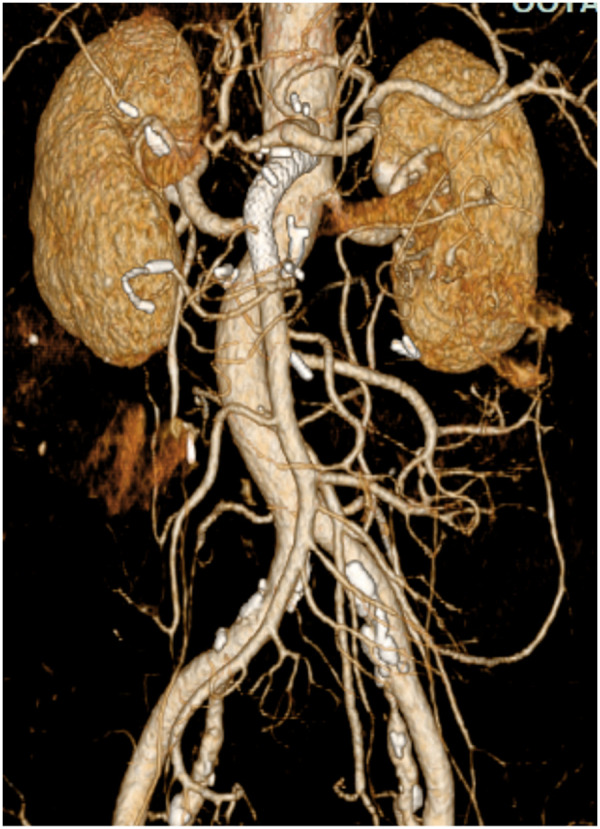

A superior mesenteric arteriovenous fistula (SMAVF) following gastrointestinal surgery represents a rare vascular complication. Enhanced computed tomography with 3-dimensional reconstruction proves to be the most efficacious modality for detecting this uncommon entity. Superior mesenteric angiography becomes imperative to accurately delineate the location and extent of mesenteric vessel involvement, which is essential for devising an optimal treatment strategy. Recently, endovascular therapy has garnered significant favor due to its less invasiveness compared to surgical interventions. Herein, we present a case of SMAVF after pancreaticoduodenectomy, manifesting with symptoms indicative of portal hypertension. Successful endovascular fistula closure using a balloon-expandable stent graft was achieved.